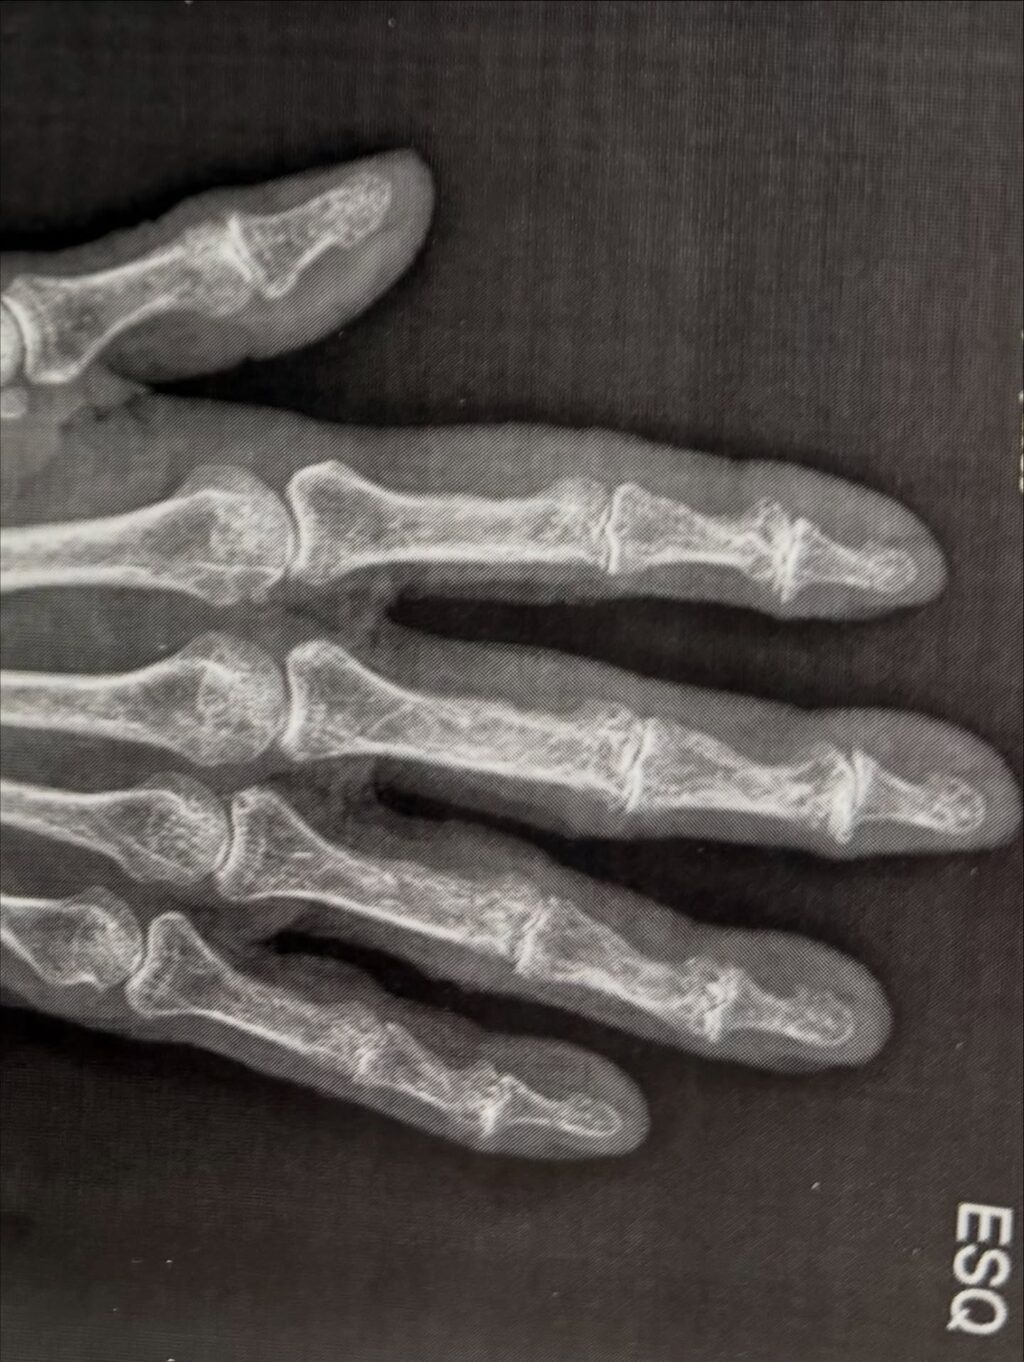

Inflamação nas articulações

Quadris, ombros ou joelhos…

A dor de espalha além das costas. Atividade como subir escadas ou realizar caminhadas se tornam dolorosas. Isso limita sua independência diária.

Através de abordagens humanizadas, a Dra. Natália trata essas inflamações, ajudando a recuperar mobilidade e conforto em todo o corpo.

Através de abordagens humanizadas, a Dra. Natalia trata essas inflamações, ajudando a recuperar mobilidade e conforto em todo o corpo.